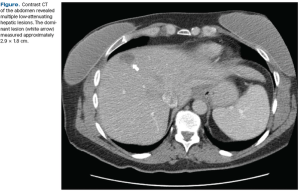

The patient presented to her primary care physician 3 months prior with an inverted left nipple and a palpable lump that was highly suggestive of neoplasm on mammogram. An ultrasound-guided core biopsy revealed an infiltrating solid-type ductal carcinoma in situ. The estimated size of the mass was approximately 1 cm. She had no symptoms suggestive of metastatic disease.